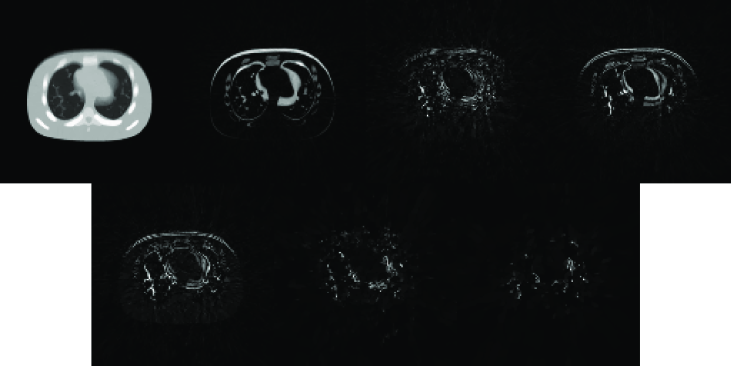

To further look into the reconstruction results, we plot the columns of 𝑳𝑳\bm{L} in Figure 4(a), where each column is reshaped into a 128×128128128128\times 128 image. These images form the basis to represent all the reconstructed cine-CBCT images. It is observed that the first one is similar to an image averaged over all the cine-CBCT images. Its presence provides an overall structure that is common to all the images in the cine-CBCT. Meanwhile, other basis images represent differences between images of 𝑼𝑼\bm{U}. We also plot the corresponding coefficients in 𝑹𝑹\bm{R} in Figure 4(b), which attain a periodically variation pattern, indicating the patient respiratory motion.

Refer to caption

(a) The columns of 𝑳𝑳\bm{L}. Each column is reshaped into an image.

(b) The rows of 𝑹𝑹\bm{R}.

Figure 4: 𝑳𝑳\bm{L} and 𝑹𝑹\bm{R} in the cine-CBCT image reconstruction from noiseless data.